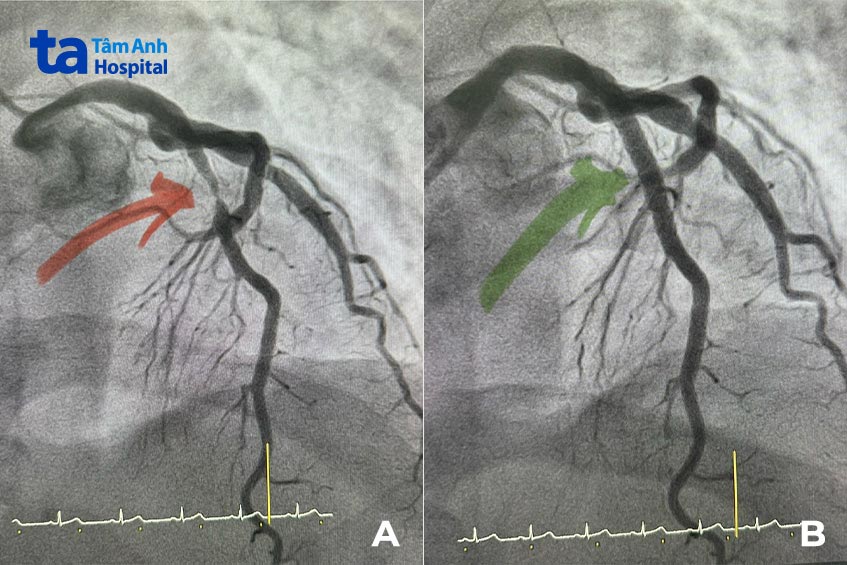

BS.CKII Huỳnh Ngọc Long, Giám đốc Trung tâm Can thiệp Mạch chia sẻ, vị trí đoạn mạch liên thất trước hẹp nằm ngay dưới cầu cơ mạch vành (chỉ cách cầu cơ 6 mm) nên rất dễ khiến bác sĩ chẩn đoán nhầm là do cầu cơ mạch vành và không cần can thiệp. Tuy nhiên, quan sát kỹ trên phim chụp MSCT mạch vành, bác sĩ phát hiện động mạch liên thất trước tắc hẹp là do mảng xơ vữa, cần can thiệp tái thông ngay để ngăn ngừa nguy cơ nhồi máu cơ tim.

Vị trí hẹp nằm gần sát cầu cơ mạch vành, đòi hỏi bác sĩ thao tác tỉ mỉ, chuẩn xác khi đặt stent để stent không bị đè ép dẫn tới gãy, móp, tăng nguy cơ tái hẹp sau này. Nhờ sự hỗ trợ của hệ thống siêu âm trong lòng mạch – IVUS, ê kíp xác định được vị trí “thả stent” né nơi cầu cơ bắt qua mạch vành, đặt stent kích thước 3.5 mm vào lòng mạch hẹp.

Siêu âm sau thủ thuật cho thấy stent áp sát mạch máu, dòng chảy đưa máu đến nuôi cơ tim được khơi thông. Đặc biệt, stent nằm đúng vị trí hẹp, không bị cầu cơ ép sát. Anh Toàn hết hẳn cơn đau thắt ngực, xuất viện ngay hôm sau. Anh được bác sĩ kê toa thuốc để tiếp tục điều trị bệnh cầu cơ mạch vành.